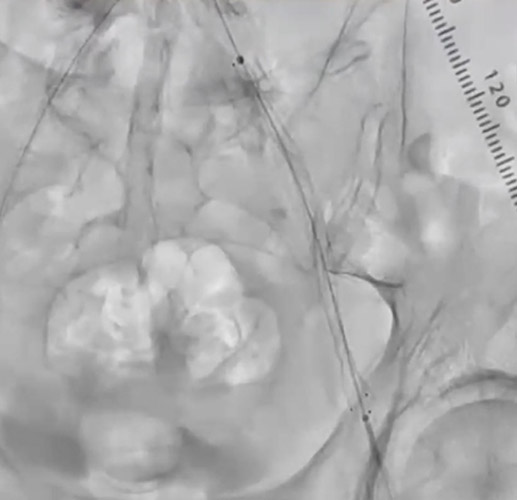

EIAの動脈瘤部にはカバードステントを留置することにした。6gワイヤー(0.014“)のままカバードステントのデリバリーを試みるが、バックアップが弱くEIAまで到達できなかった。6gワイヤーからサポート性の高い0.018ワイヤーに交換したが、ワイヤーが末梢まで到達できなかった。ラジフォーカスガイドワイヤーMスティッフ(0.035”)に交換することでサポート性を更に高めてデリバリーをし、カバードステントがIIA入口を塞がないように出来るだけ奥までデリバリーして留置した(図5)(図6)。